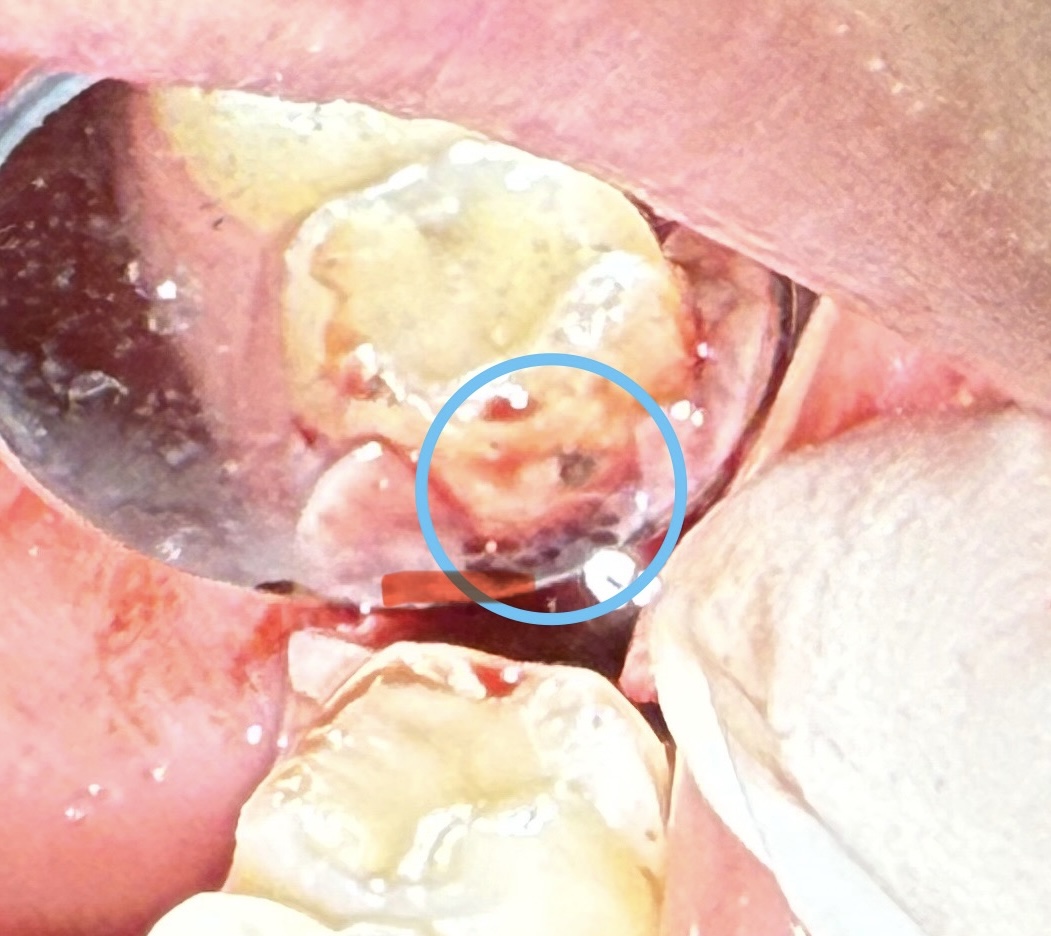

抜歯をしたあと、隣の歯をチェック!

やっぱりむし歯になっていました。

親知らずの周囲は、歯ブラシがやりにくい環境です。あるだけで、